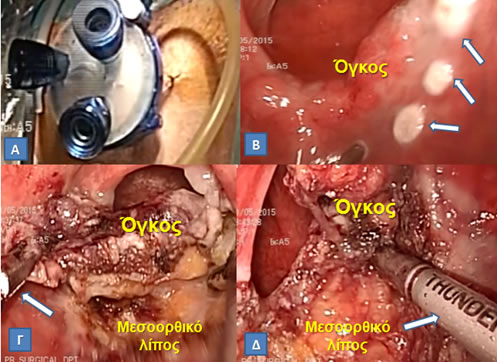

Εικόνα 18.

Διαπρωκτική αφαίρεση (Α, Β) υποβλεννογονίου στρωματικού όγκου (Gastrointestinal Stromal Tumor, GIST) ορθού (Γ). Η χρήση αυτοσυγκρατούμενου συστήματος πλαισίου-αγκίστρων Lone Star διευκόλυνε την επέμβαση.

(Από το προσωπικό αρχείο του Γ. Θεοδωρόπουλου)

Εικόνα 19.

Α. Διαπρωκτική ελάχιστα επεμβατική χειρουργική (Transanal Minimally Invasive Surgery, TAMIS) με το ειδικό κανάλι πρόσβασης στο οποίο εισάγονται 3 μικρά trocars Το ορθό διατείνεται με εμφύσηση διοξειδίου άνθρακα (όπως στις λαπαροσκοπικές επεμβάσεις).

Β. Tα όρια εκτομής σημειώνονται στον ορθικό βλεννογόνο πέριξ της βλάβης με μονοπολική διαθερμία.

Γ, Δ. Με σύλληψη του όγκου με λαπαροσκοπική λαβίδα (Γ, βέλος), η εκτομή γίνεται σε όλο το πάχος έως και το μεσοορθικό λίπος και διευκολύνεται από τη χρήση ενέργειας διατομής-αιμοσυγκόλλησης για ελαχιστοποίηση της αιμορραγίας (Δ, βέλος).

(Από το προσωπικό αρχείο του Γ. Θεοδωρόπουλου)